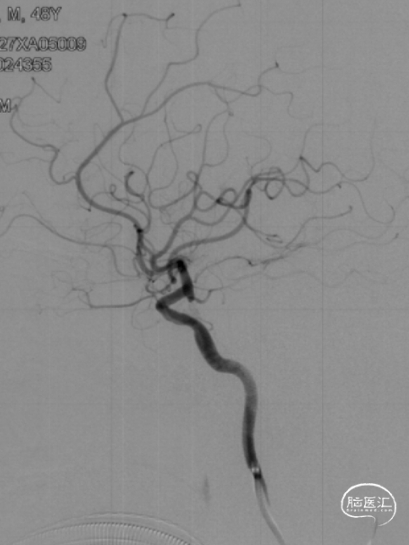

复查脑血管造影示:右侧大脑中动脉支架置入术后,支架位置良好,管腔内血流通畅,未见明显狭窄。

术后2年随访:

复查脑血管造影示:右侧大脑中动脉支架置入术后恢复良好,支架位置精确无误,其管腔血流通畅,未见任何明显狭窄,手术效果满意。

2024-08-07 2Y-FU (正位)

2024-08-07 2Y-FU (侧位)